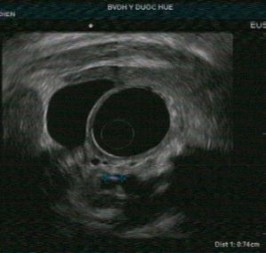

Tổn thương ống tụy: sỏi ống tụy chính, giãn ống tụy, thành của ống tụy chính không đều, tăng âm thành ống tụy chính. Nhu mô tụy thấy các nốt và dải tăng âm. Chẩn đoán chắc chắn viêm tụy mạn với tiêu chí chính A và bốn tiêu chí phụ.

Tổn thương ống tụy: ống tụy chính không giãn nhưng có tăng âm thành ống tụy. Nhu mô tụy: tổn thương dạng tổ ong, các nốt tăng âm không có bóng lưng kèm các tổn thương trống âm. Chẩn đoán nghi ngờ viêm tụy mạn với 1 tiêu chí chính B kèm 3 tiêu chí phụ.